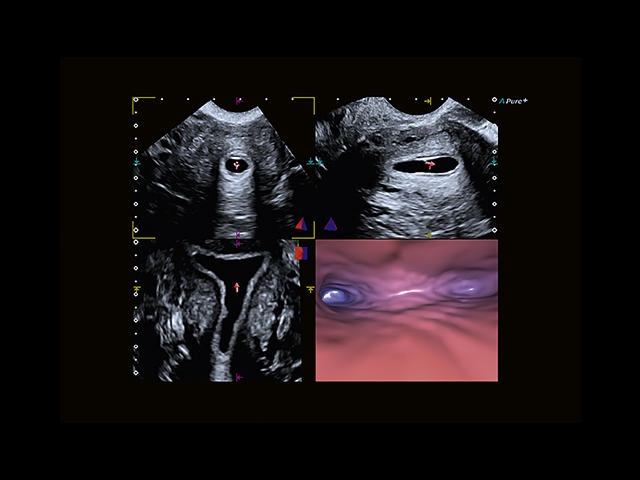

Обновленная версия легендарного УЗ-сканера. Стационарный аппарат экспертного класса Aplio 500 Toshiba NEW, визуализирует анатомические структуры в высоком разрешении. Модель позволяет выявить микрокальцификаты, новообразования, нарушения в работе сердца, сосудов и мышц. Присутствует функция виртуальной эндоскопии, 4D-сканирования, эластометрии тканей, УЗИ с контрастированием. За повышение качества изображения отвечают технологии ApliPure и Superb Microvascular Imaging. Первая задействует возможности пространственного и частотного кодирования, формирует цельный визуальный ряд с сохранением клинических маркеров. Вторая улучшает отображение микрососудистого русла, используя доплеровский эффект. Модель оснащена 21-дюймовым монитором, имеет 4 активных порта. Возможно подключение педиатрических, интраоперационных, лапароскопических и чреспищеводных датчиков.

- Fly Thru. Виртуальная эндосонография обеспечивает построение трехмерной модели полостей, протоков и сосудов в рельном времени, облегчает организацию инвазивных процедур и динамических исследований. Посредством Fly Thru можно установить шунты и стенты, проводить точные оперативные вмешательства.